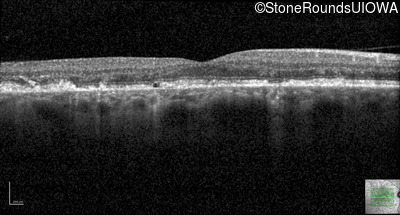

Optical Coherence Tomography - Right - 20/40 +2 sc

Exemplar / OCT Stack